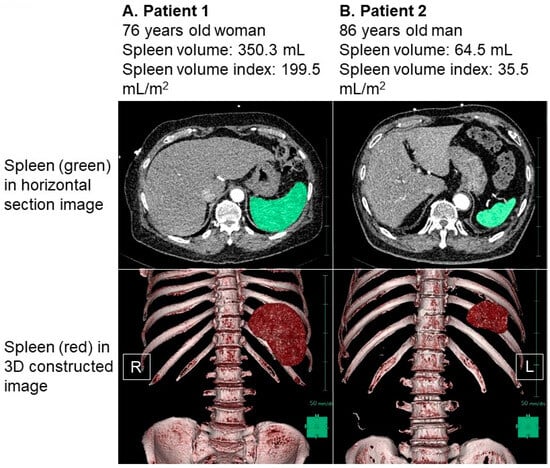

The distribution of the baseline SVI values exhibited considerable variability, with a median SVI of 65.5 (48.9, 86.9) mL/m2 (Figure 2). For illustrative purposes, representative cases of a low SVI and a high SVI were presented in Figure 3A and Figure 3B, respectively.

In Figure 3A, we observe a 76-year-old female patient who had a body height of 160 cm and a body weight of 72.3 kg, resulting in a body mass index of 28.2. Her splenic volume was measured at 350.3 mL, and when indexed to her body surface area, it amounted to 199.5 mL/m2. Figure 3B showcases an 86-year-old male patient with a body height of 161 cm and a body weight of 76.8 kg. His splenic volume was measured as 64.5 mL, and when indexed to his body surface area, it equated to 35.5 mL/m2.

As an illustrative example, the patient represented in Figure 3A, characterized by an elevated SVI, exhibited a plasma volume status of −9.5% and a cardiac index of 2.44 L/min/m2. In contrast, the patient illustrated in Figure 3B, with a low SVI, displayed a plasma volume status of −36.3% and a cardiac index of 1.93 L/min/m2.

Figure 3. Representative cases of high splenic volume index (A) and low splenic volume index (B). Spleen was colored in green in horizontal section image and was colored in red in three-dimensional constructed image. (A) Patient 1 was 76-year-old woman. Body height was 160 cm and body weight was 72.3 kg. Her splenic volume index was calculated as 199.5 mL/m2. (B) Patient 2 was 86-year-old man. His body height was 161 cm and body weight was 76.8 kg. His splenic volume index was calculated as 35.5 mL/m2. Splenic volume was larger in patient 1 compared to patient 2 in both 2-dimensional and 3-dimenstional imaging. R, right; L, left.